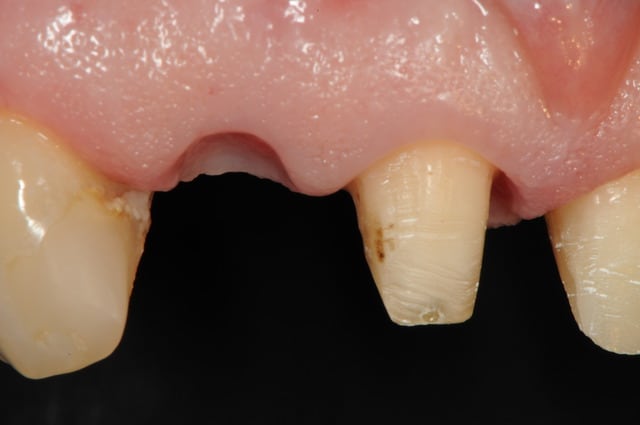

deux mois après (photo 2-3-4), l'état de la gencive me paraît plutôt sympa et je propose donc d'en rester là. toutefois la patiente ne veut pas, elle à peur de perdre le bridge (même le définitif) , bref, elle veut un implant !

je jour J, à l'heure H, je fini par poser mon implant.

il reste même après deux mois encore des saletés (photo2)

photo

3- axe implantaire

4-5 pose implant et comblement